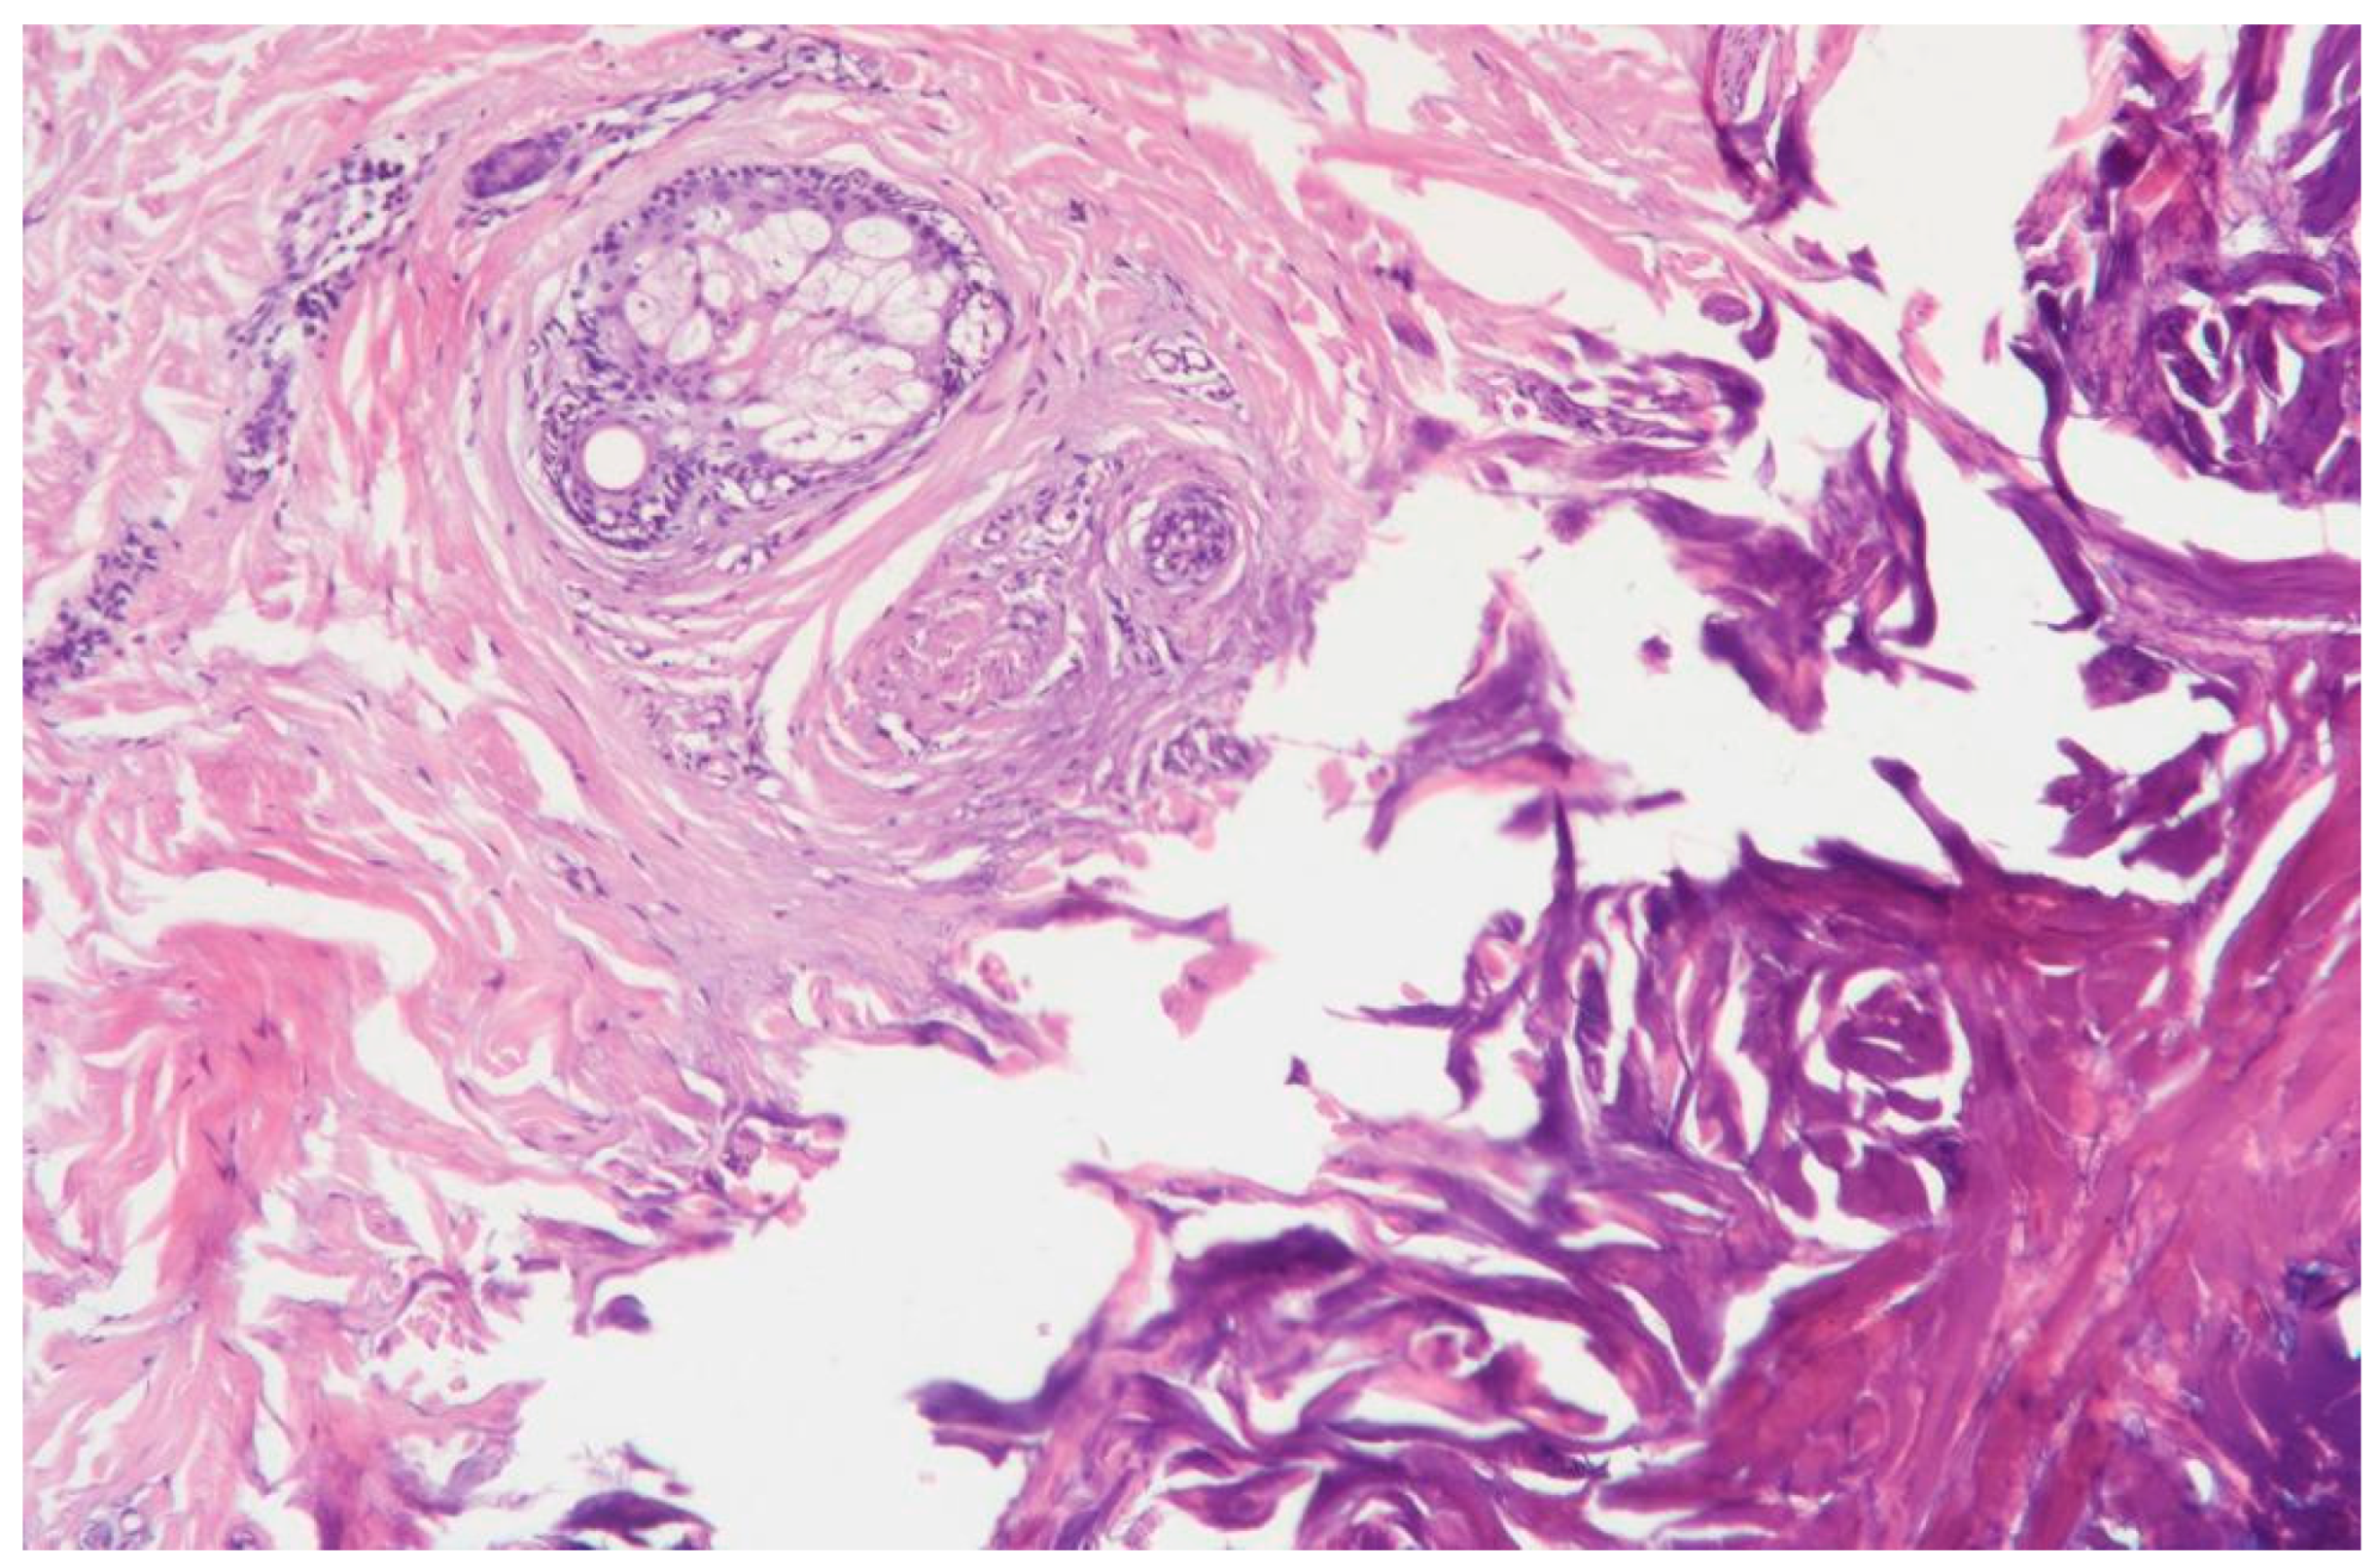

3.1.5. Clinical Case 5: Skin Dissection Area, Scar 15 W (See Figure 6)

Description: There was extensive coagulative necrosis of the tissues, the vessels were coagulated, and hemorrhages were absent.

Figure 6. Skin changes following exposure to the thulium laser at 15 W, 75 Hz. H&E staining, 10× objective magnification.

3.1.6. Clinical Case 6: Skin Dissection Area, Scar 20 W (See Figure 7)

Description: The coagulative necrosis zone was less deep, with no inflammatory changes observed. The vessels in the treated area were coagulated. In the surrounding tissues, collagen fibers and skin appendages were preserved. A slight polarization of the nuclei of skin appendage cells was noted at the boundary between the coagulative necrosis zone and the intact tissues. The vessels in this area were dilated, with no signs of hemorrhage, and the subcutaneous adipose tissue remained intact.

Figure 7. Skin changes following exposure to the thulium laser at 20 W, 100 Hz. H&E staining, 10× objective magnification.

Thus, when exposed to the thulium laser at 20 W, the surrounding tissues exhibited the least pronounced necrotic changes, with no hemorrhages or inflammatory alterations.